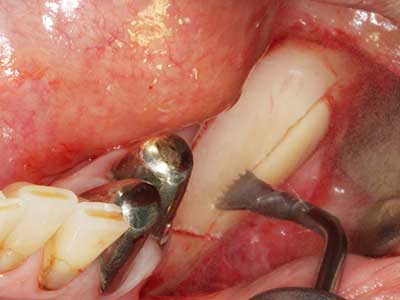

La piezochirurgia presenta altri vantaggi per quanto riguarda la raccolta di blocchi ossei. Oltre all'elevata precisione dell'osteotomia appena descritta, l'utilizzo di puntine per sega molto sottili permette di minimizzare in maniera significativa la perdita di materiale. È molto probabile che si verifichi una maggiore perdita di materiale durante la raccolta utilizzando puntine di strumenti più spessi, in particolare delle frese Lindemann (Lakshmiganthan, Gokulanathan et al. 2012). La separazione basale, necessaria in particolare per i trapianti di blocchi nella zona retromolare, viene semplificata grazie a seghe specificatamente progettate di forma rettangolare; di conseguenza la piezochirurgia è considerata una procedura precisa, semplice e sicura per la raccolta di blocchi di osso nella zona retromolare (Happe 2007) (figg. 1-12).

Fig. 1: preparazione di una copertura ossea con Piezomed (W&H Salisburgo, Austria).

Fig. 3: la separazione basale del blocco è più semplice con i raccordi appositamente angolati.